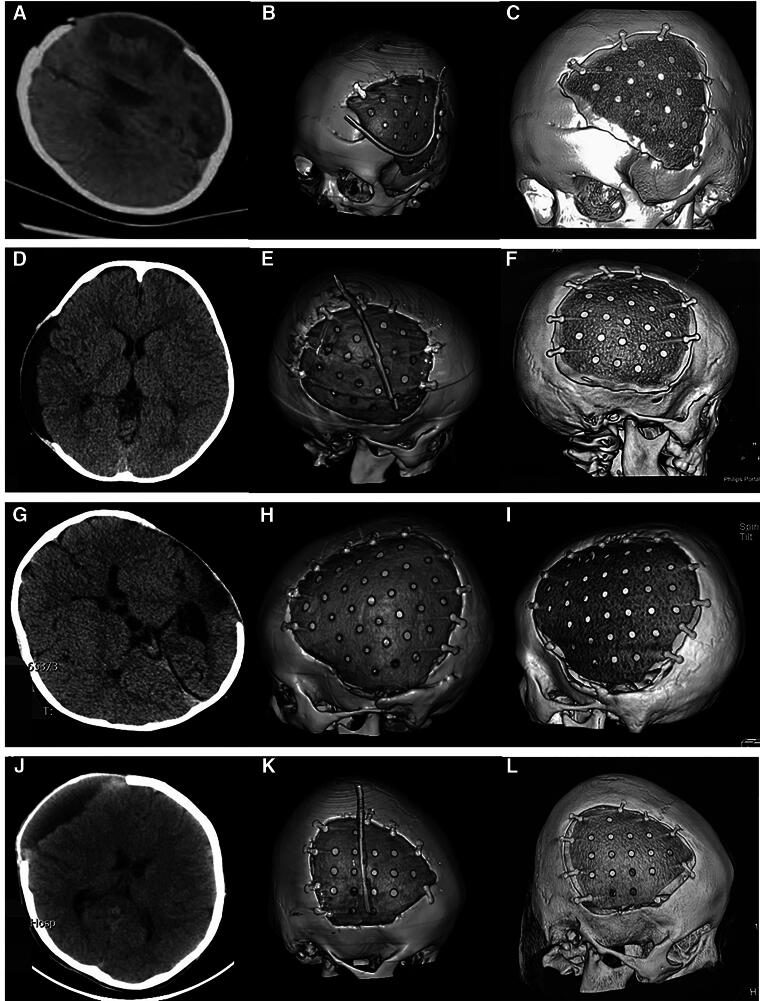

This study aimed to explore the experience and complications of cranioplasty (CP) with polyether ether ketone (PEEK) in pediatric and adolescent patients after decompressive craniectomy (DC). A total of 62 children (aged <18 years) with cranial bone defects due to DC underwent CP with a custom-made PEEK at our department between January 2018 and April 2023. The clinical characteristics, radiological features, surgical conditions, postoperative complications, and follow-up results of these patients were analyzed retrospectively. Kaplan-Meier survival analysis and Cox regression were used to analyze data. The age of the patients ranged from 2 to 17 years. The follow-up periods ranged from 12 to 70 months. Six patients experienced subcutaneous fluid accumulation (9.7%), five experienced epidural fluid accumulation (8.1%), and two experienced scalp inflammation (3.2%), which all were cured before discharge. Seven patients experienced bone gap expansion at the interface between the cranial bone and PEEK during follow-up (11.3%). Univariate analysis showed that DC-CP time interval (<3 months) and age were two influencing factors. Multivariate analysis revealed that age was the most important factor (p < 0.005, hazard ratio = 0.250, 95% confidence interval: 0.096-0.652). No reoperation was performed. Medical follow-ups were carried out further. For pediatric patients with cranial defects after DC who receive CP with a custom-made PEEK, two variables including younger age and too short DC-CP time interval may be unfavorable factors, to make patients experience bone gap expansion at the interface between the cranial bone and the PEEK. Additional data should be collected to validate our conclusions.